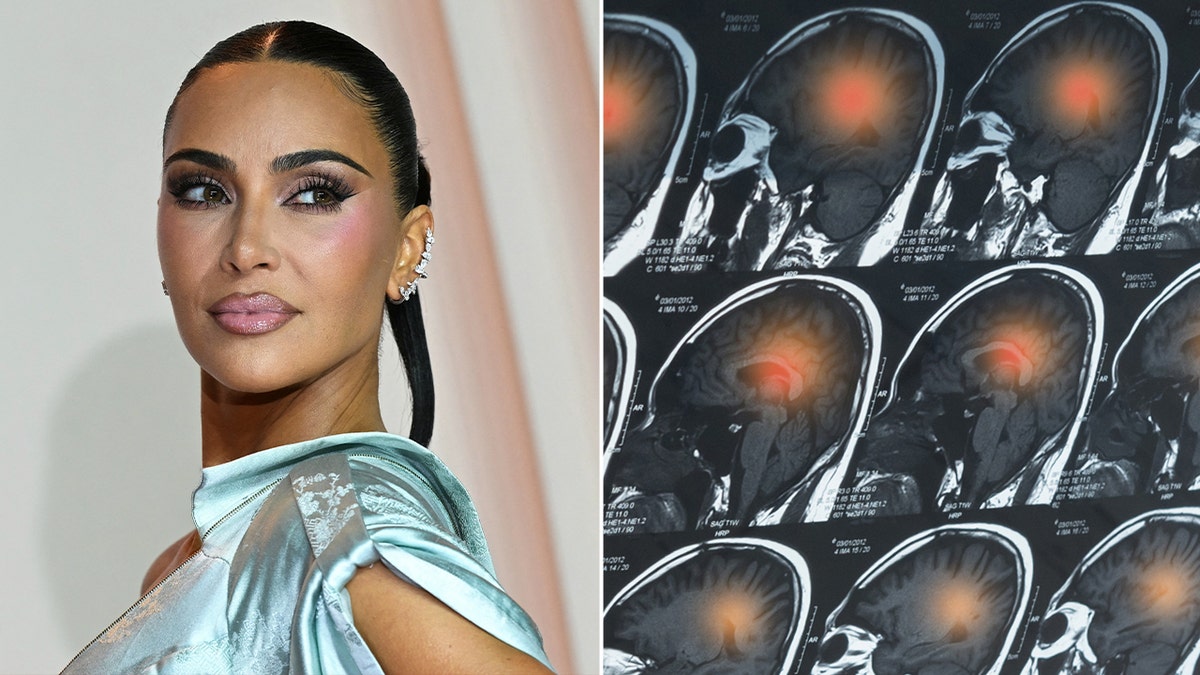

Up to one in 50 people have a brain aneurysm, which is the ballooning of an artery in the brain. (iStock)

A brain aneurysm is the ballooning of a blood vessel in the brain, which can leak or rupture, leading to bleeding, according to Mayo Clinic.

Dr. Adam Arthur, chairman of neurosurgery at the University of Tennessee, described an aneurysm as a weakness on the wall of an artery, like a little water balloon that forms off a hose.

This is known as a hemorrhagic stroke, which can be life-altering and even fatal. Most aneurysms are small and not serious if they don’t rupture.